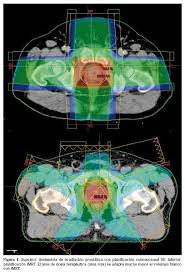

Se completó el estudio, se inició el tratamiento con Radioterapia y Quimioterapia, y se sometió a una intervención quirúrgica, con un resultado favorable: años después está libre de enfermedad.